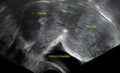

-

A very large (9 cm) fibroid of the uterus which is causing pelvic congestion syndrome as seen on ultrasound